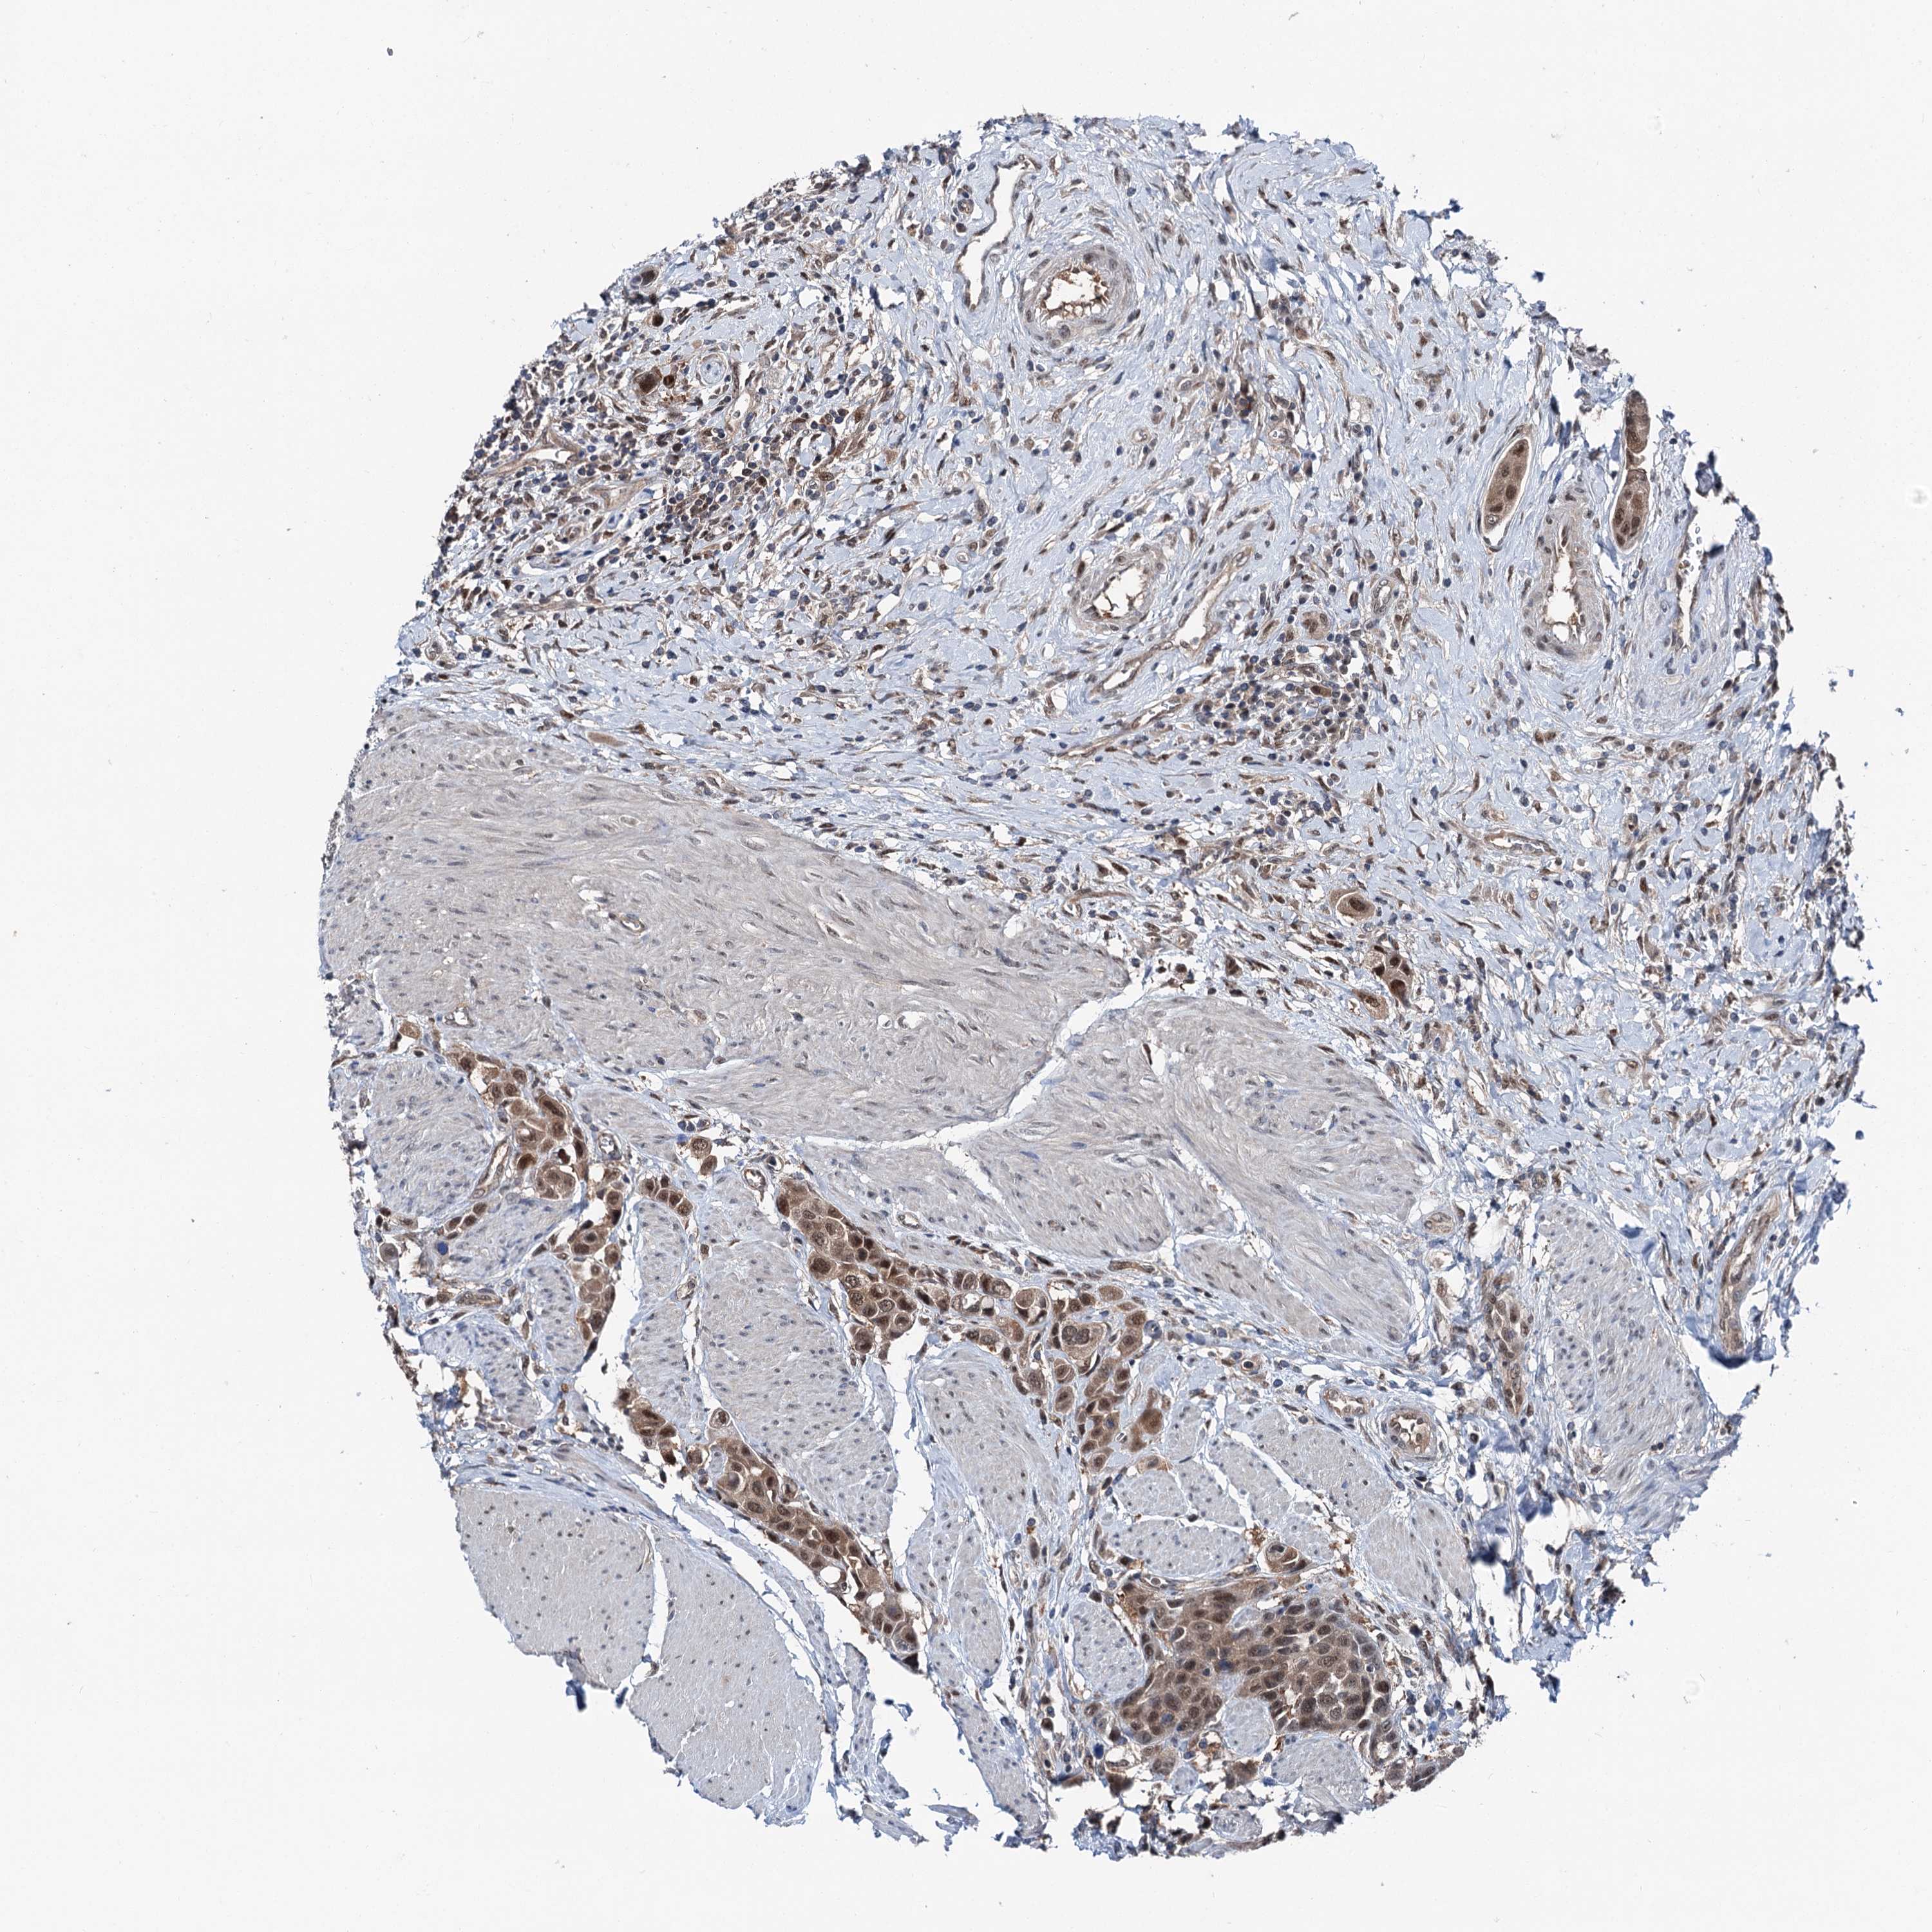

UROTHELIAL CANCER - Protein expressioni

A mouse-over function shows sample information and annotation data. Click on an image to view it in a full screen mode. Samples can be filtered based on level of antibody staining by selecting one or several of the following categories: high, medium, low and not detected. The assay and annotation is described here.

Note that samples used for immunohistochemistry by the Human Protein Atlas do not correspond to samples in the TCGA dataset.

Antibody stainingi

Antibody staining in the annotated cell types in the current human tissue is reported as not detected, low, medium, or high, based on conventional immunohistochemistry profiling in selected tissues. This score is based on the combination of the staining intensity and fraction of stained cells.

Each image is clickable and will lead to virtual microscopy that enables deeper exploration of all samples and also displays staining intensity scores, fraction scores and subcellular localization as well as patient and tissue information for each sample.

Antibody HPA038691

Antibody HPA038692

Staining

High

Medium

Low

Not detected

Intensity

Strong

Moderate

Weak

Negative

Quantity

>75%

75%-25%

<25%

None

Location

Nuclear

Cytoplasmic/membranous

Cytoplasmic/membranous,nuclear

Urothelial carcinoma, Low grade